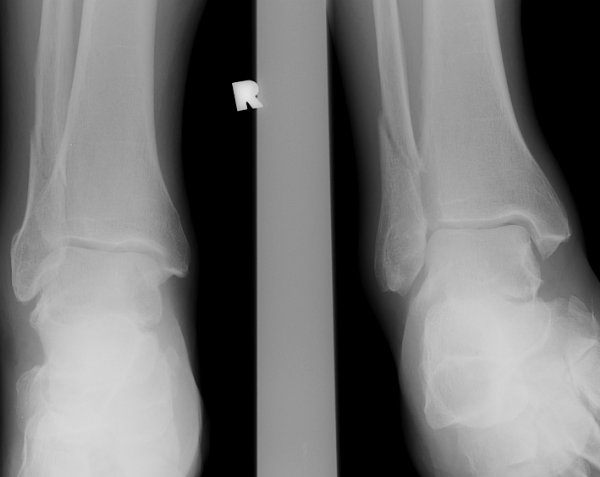

Return to Weber C Fracture